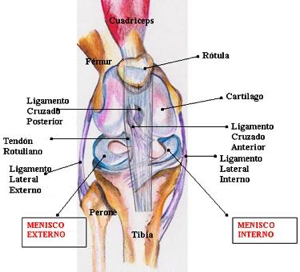

La traumatología se ocupa de las lesiones traumáticas de columna y extremidades que afectan a los huesos, ligamentos y articulaciones, músculos y tendones, entre ellos las roturas fibrilares, contusiones, tendinitis y hematomas así como heridas en la piel.

Los tratamientos conservadores que un traumatologo ortopedista realiza pueden ser las reducciones incruentas, vendajes blandos, la colocación de férulas y yesos asi como tracciones blandas ó esqueléticas. Los tratamientos quirúrgicos implican una acción sobre situaciones de mayor gravedad o que requieran cirugía como único medio de solución. Para ello se emplean: la reducción abierta, agujas de Kirschner y Steinmann, placas y tornillos de osteosíntesis, dispositivos clavo-placa y tornillo-placa, clavos intramedulares (Küntscher, Gross-Kempf, Ender, Russ), fijadores externos (Hoffman, Ilizarov, monolaterales), injertos óseos, cementos óseos y prótesis para reemplazos articulares.